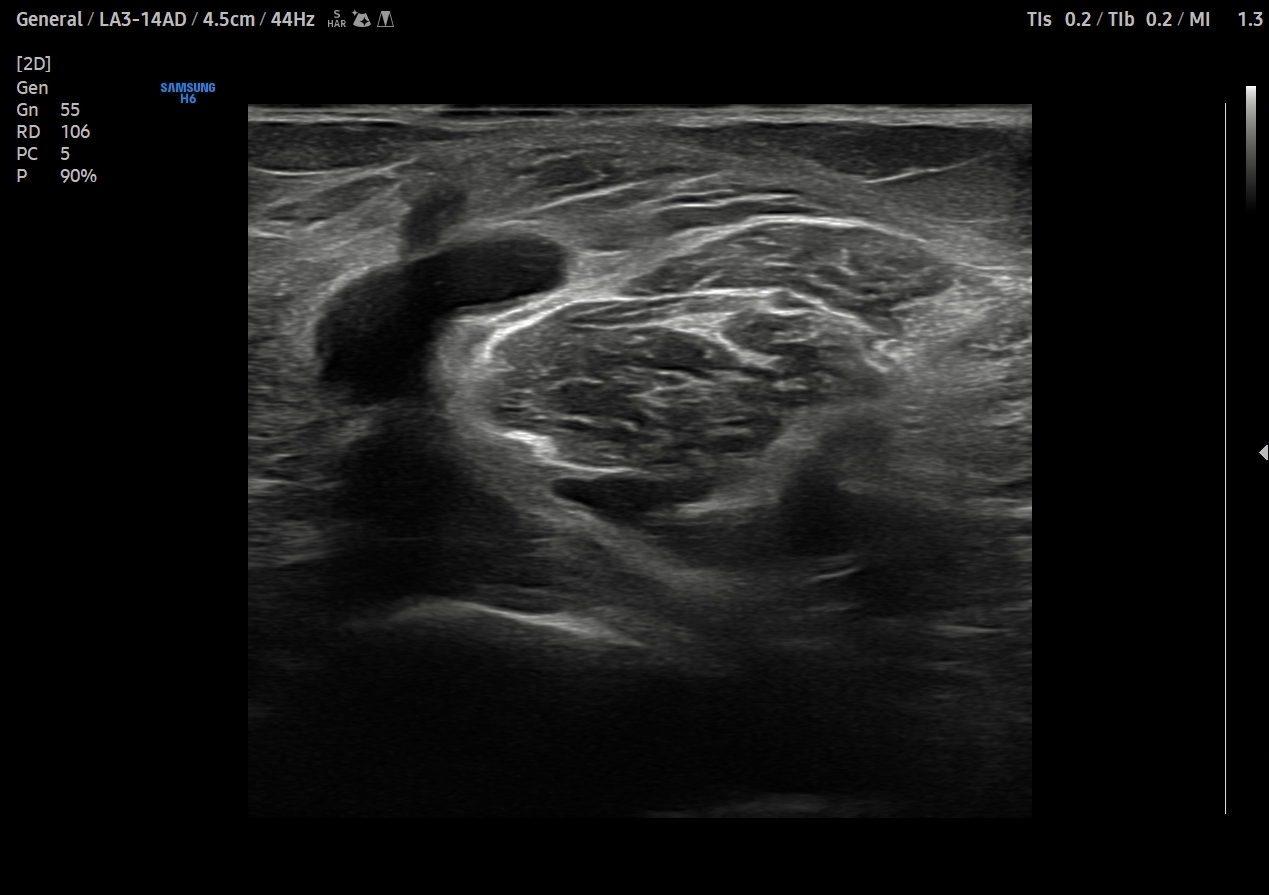

Descripción de los hallazgos ecográficos y las imágenes más relevantes para la resolución del caso

Se explora cara anterior, lateral y medial de rodilla sin hallazgos significativos. En cara posterior se explora el hueco poplíteo donde se visualiza en corte transversal una estructura hipoecoica con la base, el cuello entre el tendón del semimembranoso y el tendón de la cabeza medial del gemelo interno y el cuerpo. Sin signos de complicación. Permeabilidad del sistema venoso profundo.